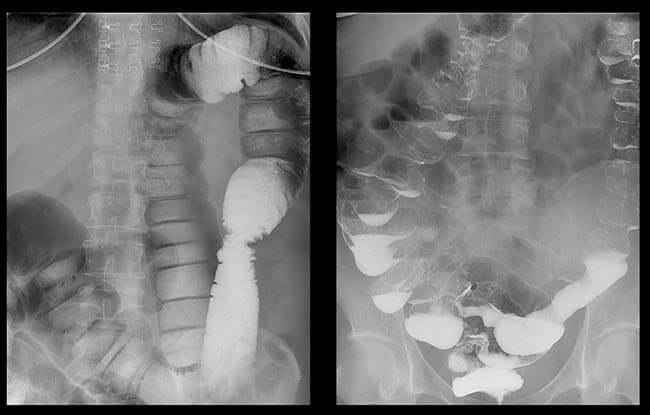

Colon cancer in a woman complaining of frequent constipation

X-rays of callous stones in the colon